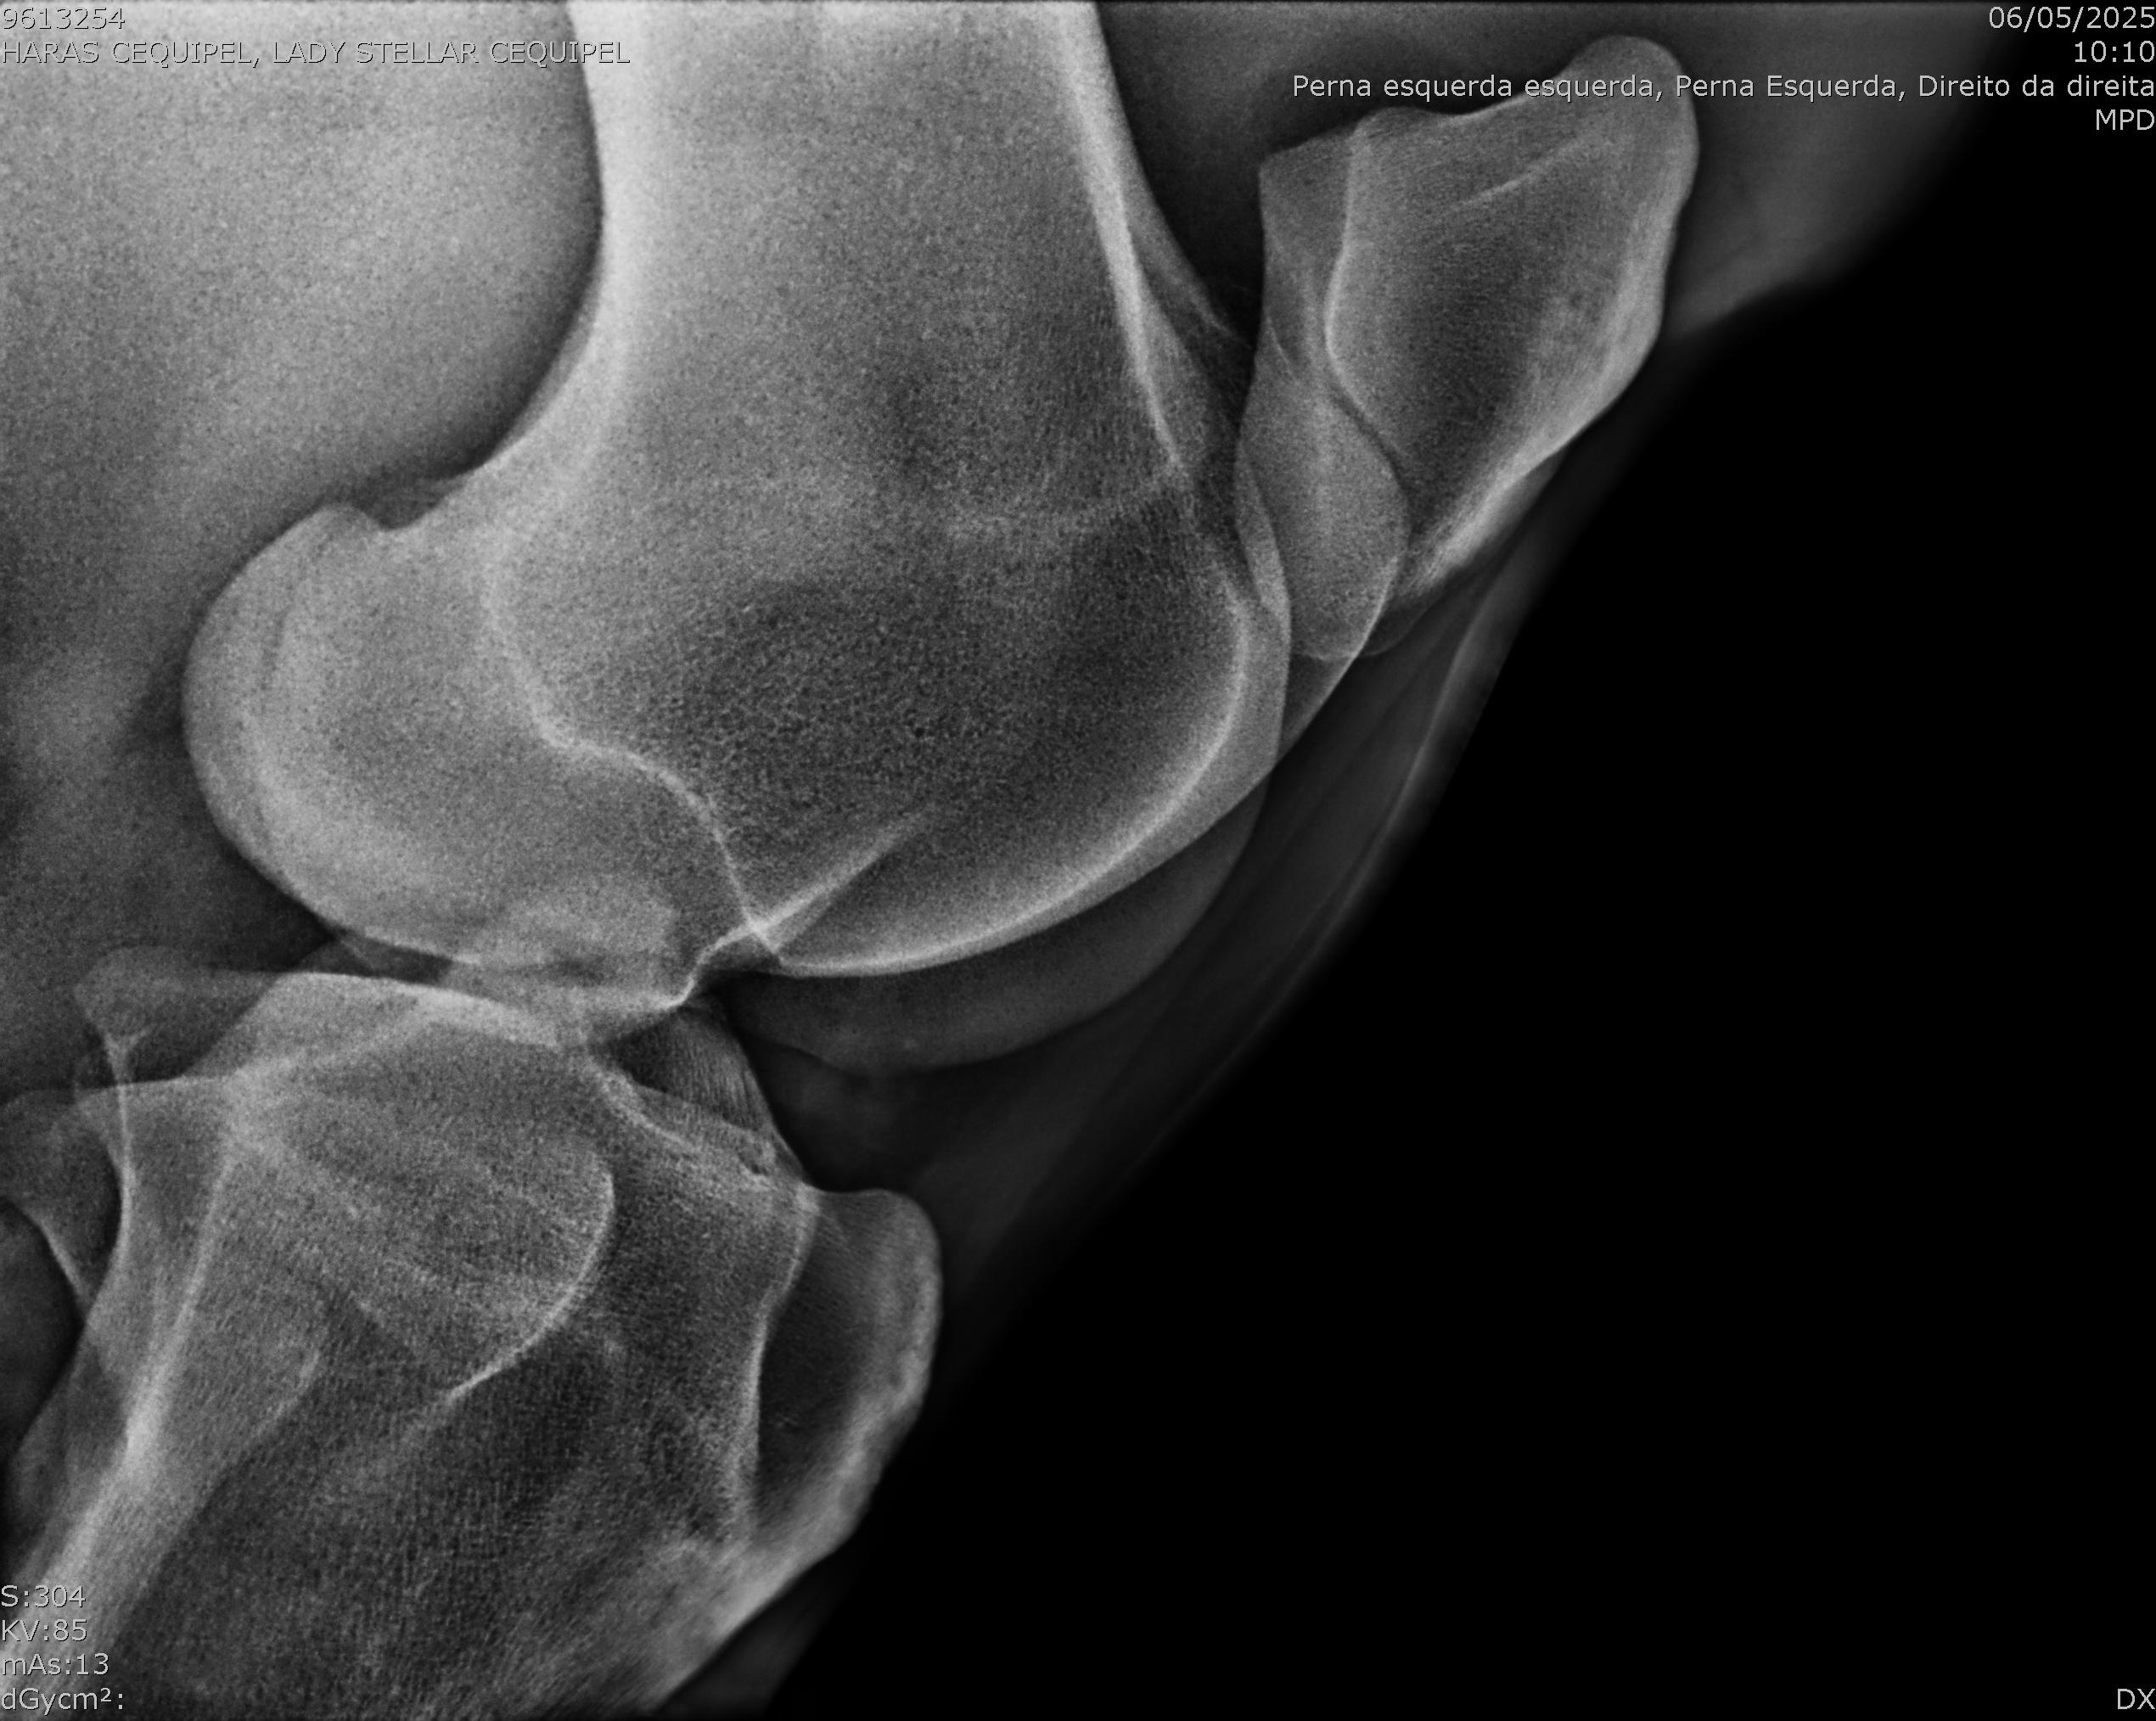

:: RAIOS-X DO LOTE